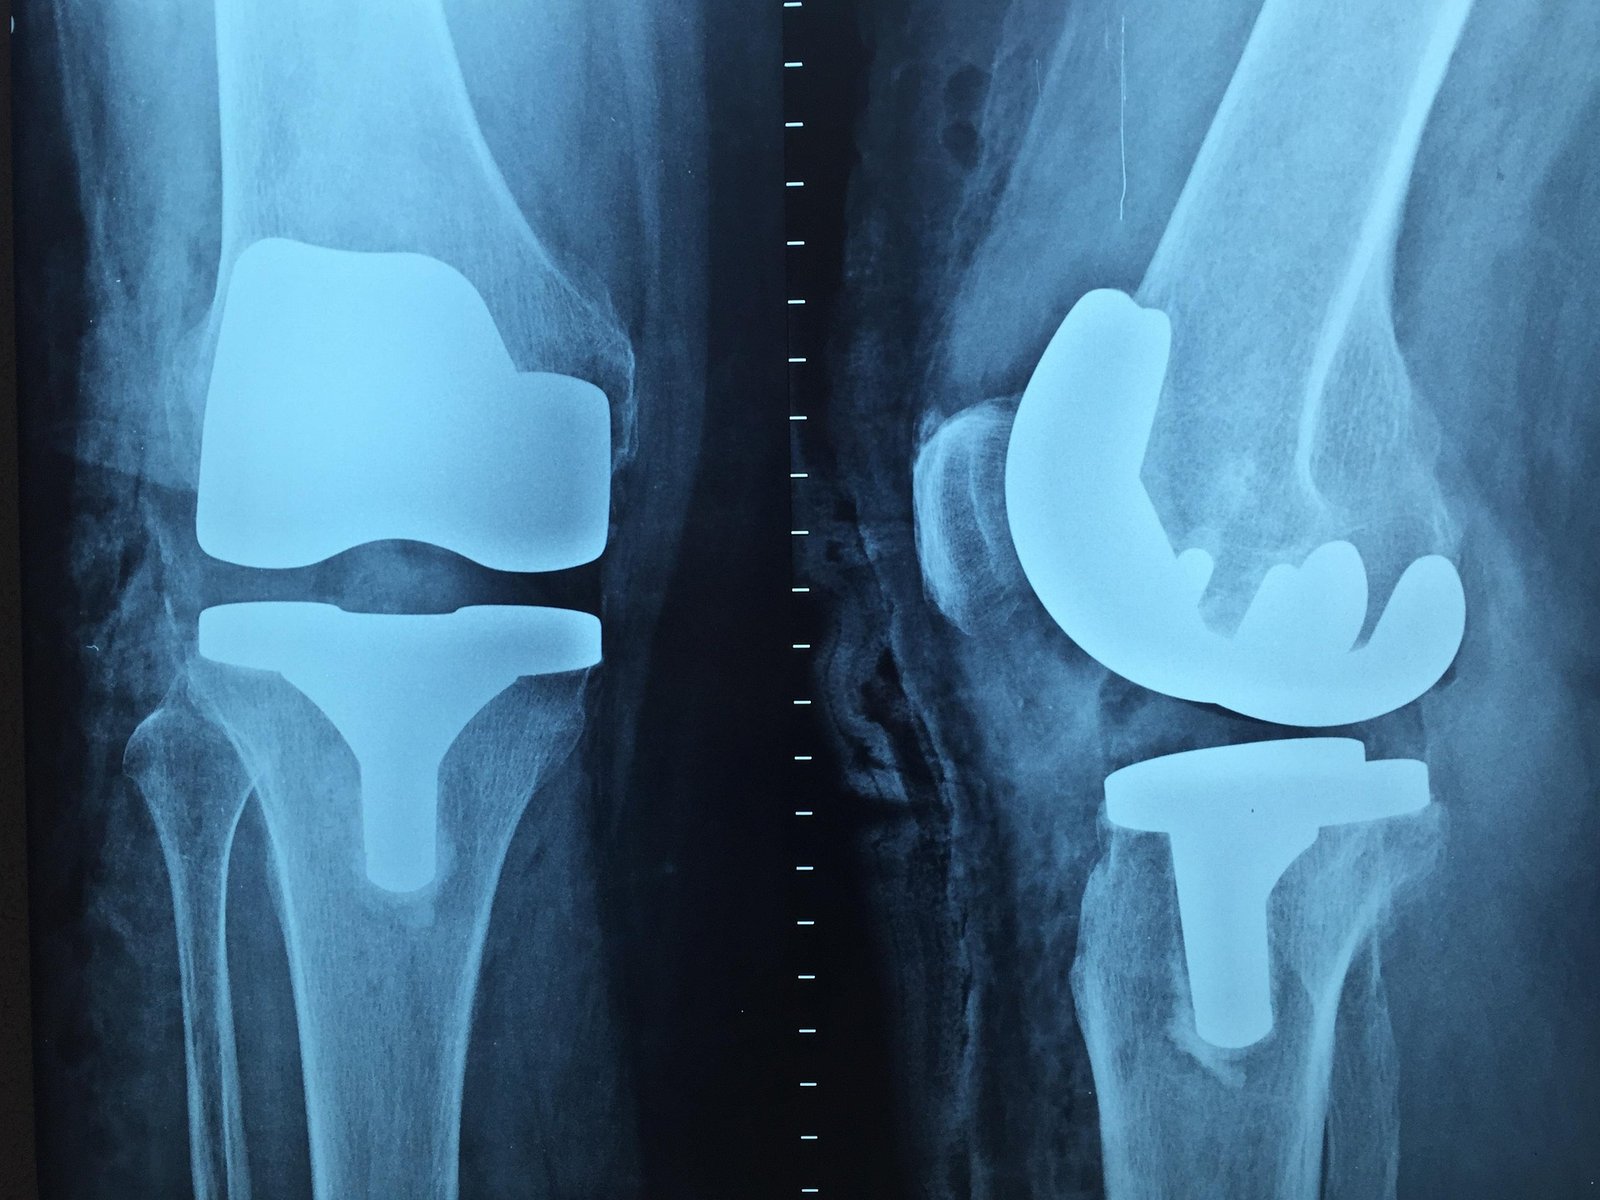

Harnessing cutting-edge robotic technology and evidence-based techniques, we provide highly precise joint replacement and sports injury treatments designed for quicker recovery, reduced pain, and long-lasting results.

Joint preservation focuses on delaying or preventing joint replacement in patients with early to moderate arthritis.